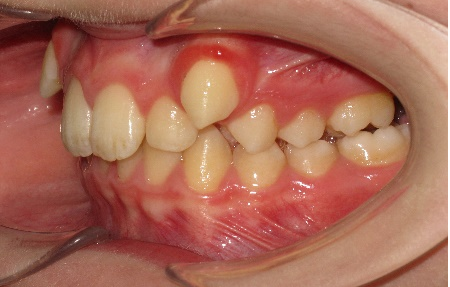

В полости рта: смыкание первых моляров по дистальному типу. Сужение зубных рядов в боковых отделах. 13 и 23 - вестибулярное и супраположение с дефицитом места в зубном ряду на величину ширины коронки клыка. Глубокая резцовая окклюзия.(рис.2.)

Рис.2.Смыкание зубных рядов пациента А. до лечения и окклюзионный вид.